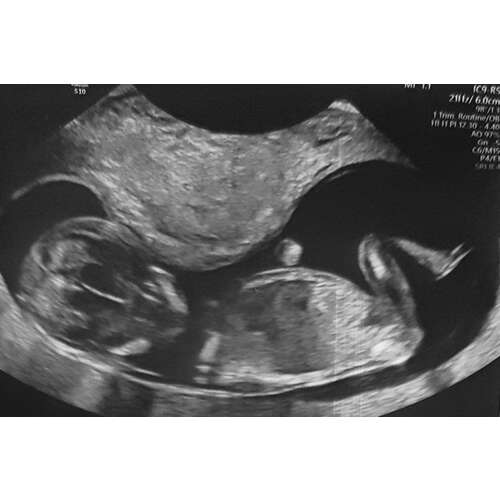

Hey! Ik heb me laten vaccineren met Pfizer op "2 weken" en 6 weken.

Gisteren op 12 weken een termijnecho gehad en alles is nog steeds goed, alles zit erop en eraan en het hartje klopt mooi. Baby groeit ook netjes volgens de opgestelde regeltjes. Ook is de baby ontzettend aan het bewegen.

Ik heb van beide vaccinatie geen last gehad, we hebben 3 weken geleden de 20 weken echo gehad en alles was gezond en goed.

Ik ben gevaccineerd tijdens mijn zwangerschap. Beide keren pfeizer gehad. Ik heb nergens geen last van gehad en de kleine doet het super. Vandaag 35 weken zwanger en een liggingsecho gehad. Alles was goed!